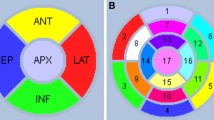

Images were processed using filtered back projection using a Hann filter cutoff at one cycle per centimeter. Attenuation correction was derived by segmenting the transmission image using the method of Xu et al. [13] as implemented by the scanner manufacturer. The transaxial images for all cardiac scans were resliced, and the short axis images saved for processing in our processing and quantization software (Emory Cardiac Toolbox, Atlanta, GA, USA) including quantitative comparison to a normal file described elsewhere [14–17].

Quality Control Program

After reconstruction, the transmission and emission images were entered into a quality control program to assess the amount of misregistration [See below for screen captures of the quality control (QC) program]. A modification of the method of Loghin et al. [7] was used to quantitate the amount of misregistration. Briefly, a threshold of 0.05/cm was used to convert the raw transmission image to a binary image. This threshold effectively differentiates between lung and tissue regions in the attenuation map. A seed was automatically placed inside the left lung, and a region-growing routine was used to segment the left lung from the image. Then, the emission image was converted to a binary image using a threshold of 0.3 times the maximum pixel value in the emission image. Finally, the overlap between the segmented left lung and emission binary images was determined. The overlap was quantitated both in terms of the number of pixels and volume (ml).

Misalignment Evaluation

One board-certified nuclear medicine physician (RH) and one board-certified nuclear radiologist (DMS) used the QC program to determine if the lateral wall of the myocardium on the emission map overlapped with that of lung on the transmission images. Misalignment of left ventricular emission activity to lung attenuation on the stress and rest exams was assessed and recorded in terms of pixels and size in cubic centimeters. Pixel size is 0.088 cc (0.51 × 0.51 × 0.34 cm).